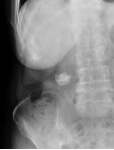

1胆系结石症X线表现:平片PTCT

CT表现:平扫呈单发或多发圆形高密度影;肝内胆管结石:常为高密度,呈与肝内胆管走行一致的结节状影,常伴有周围胆道扩张;胆总管结石:多为高密度。结石上部胆管扩张。可见“环靶”征或“半月”征。